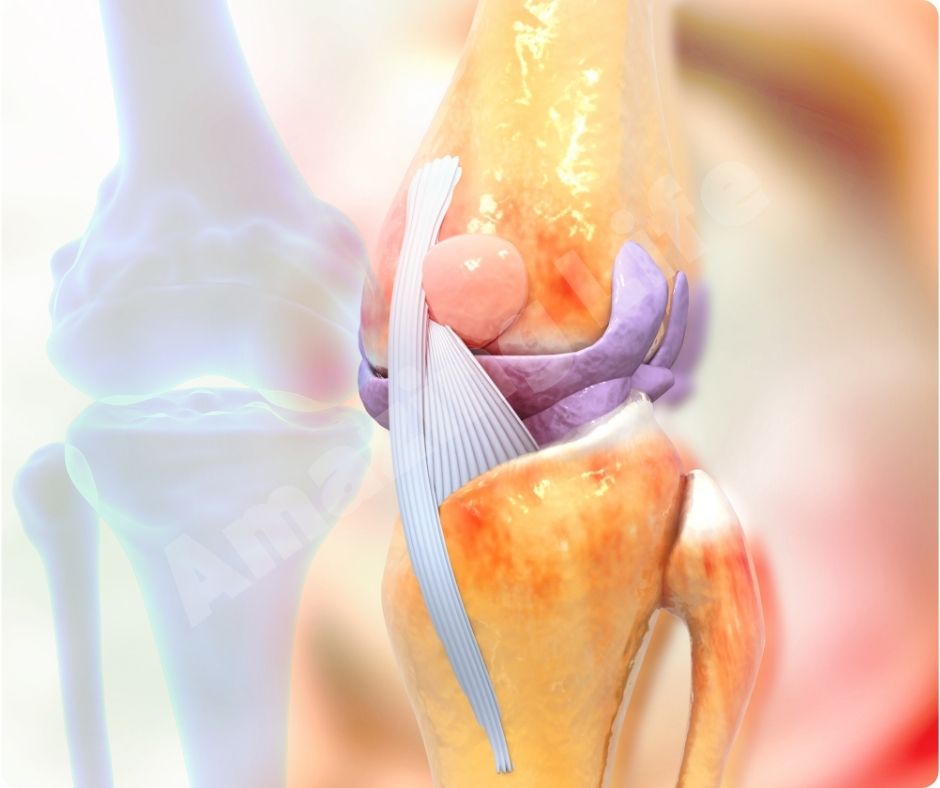

콘드로이친은 우리의 관절을 보호하고, 연골의 구조와 기능을 유지하는 데 중요한 역할을 하는 물질입니다. 주로 관절염 치료에 사용되며, 연골의 분해를 늦추고 통증을 완화하는 데 도움을 줍니다.

콘드로이친 효능은 특히 골관절염 환자들에게 효과적입니다. 여러 연구에 따르면, 콘드로이친이 연골의 분해를 억제하고, 연골을 보호하며, 통증을 줄이는 데 도움을 준다고 합니다. 2023년의 한 연구에서는 콘드로이친과 글루코사민을 함께 섭취하면 무릎 관절염의 진행을 늦출 수 있다고 보고했습니다.

콘드로이친은 항염증 작용이 있어 관절염 환자들에게 특히 유익합니다. 염증을 줄여 관절 통증을 완화하고, 전반적인 관절 기능을 개선하는 데 도움이 됩니다. 이는 특히 만성 염증 질환을 앓고 있는 사람들에게 큰 도움이 될 수 있습니다.